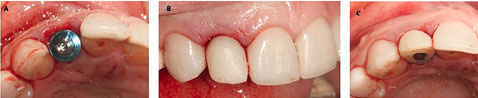

Figure 5.

(A) Placement of an Osseotite implant in the extraction socket. Immediate provisional composite-based crown from the frontal (B) and occlusal views (C)

A temporary cylindrical abutment was tightened on the implant, and a composite-based provisional crown (Dentocrown, Itena, Villepinte, France) was fabricated on the temporary cylinder to make a screw-retained provisional restoration (Figure 5B). The occlusal assessment was made, and any centric and eccentric contacts were eliminated. Amoxicillin, 500 mg (q8h for seven days), gelofen, 400 mg (q6h for seven days), and 0.2% CHX mouthwash (twice daily for a week) were prescribed. The patient was placed on a soft diet for two months.

A regular follow-up was performed every month. After four months, the site healed without any complications (Figure 6), and the periapical radiograph showed no bone loss and radiolucency around the implant. The provisional restoration was removed, and an open tray impression was taken using the putty/wash technique (ImprintTM, 3M, Minnesota, United States) (Figure 7). The implant abutment torqued to 25 N/cm2, and a definitive screw-retained metal-ceramic restoration was delivered (Figure 8).